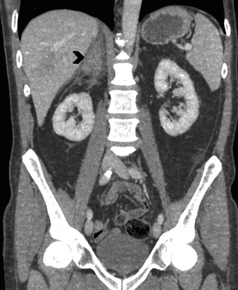

Otros hallazgos que son sospechosos de malignidad, además de los criterios morfológicos ya descritos, son metástasis concomitantes en otro sitio anatómico, heterogeneidad de su estructura, y lavado pobre del contraste en fase tardía. A menudo tienen un lavado lento, menor a un 75% luego de los 15 minutos. No es infrecuente la presencia de necrosis central y hemorragia. En TC se pueden observar como una masa de partes blandas ovoidea o redondeada, o menos frecuentemente como un aumento de tamaño difuso de la glándula suprarrenal. En fase no contrastada la mayoría de las metástasis tienen valores de atenuación mayores a 10 UH, pero existen excepciones como es el caso de las metástasis de melanoma en que los valores de atenuación pueden ser menores, cercanos a los de un adenoma típico. Utilizando estos criterios, la sensibilidad y especificidad para diferenciar mediante TC una metástasis de un adenoma es de 98 y 97%, respectivamente13.

En RM típicamente son hipointensas en secuencias ponderadas en T1 e hiperintensos en T2. La mayoría de las metástasis no muestran caída de señal en secuencias fuera de fase (Figura 20 a y b), porque no contiene lípidos intracelulares. Infrecuentemente las metástasis pueden contener lípido intracelular, como es el caso raro de metástasis de tumores de células renales.